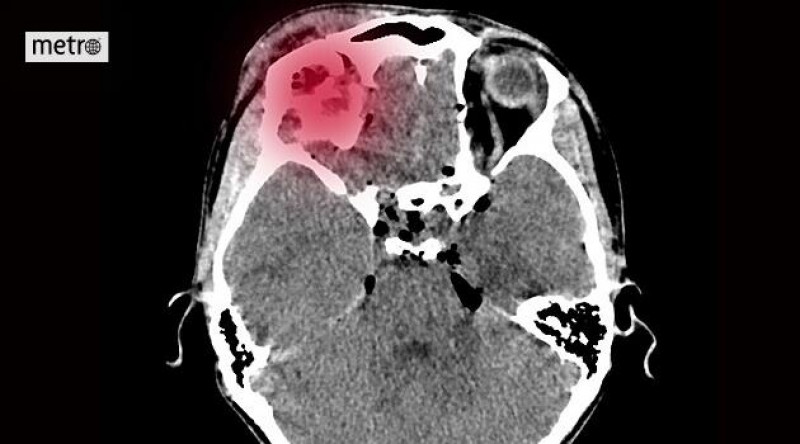

Do nemocnice přišel čtyři hodiny po mrtvici. Přerov má vlastní iktové centrum a šetří čas

155